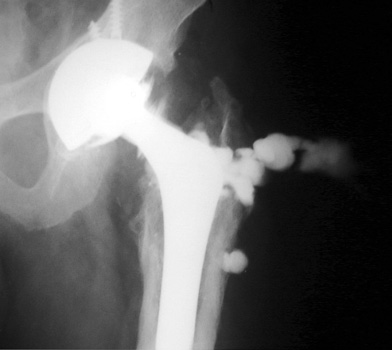

Arthrographic evidence of looseningcontrast enters

abnormally widened interface Gruen zone 1 and 2

Arthrographic evidence of cup looseningcontrast enters

abnormally widened interface Gruen zone II and III